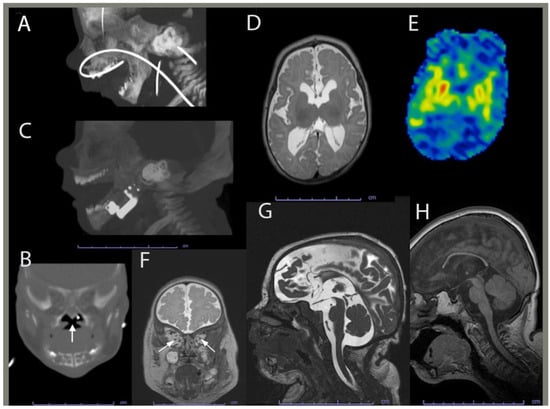

2.1. Clinical History